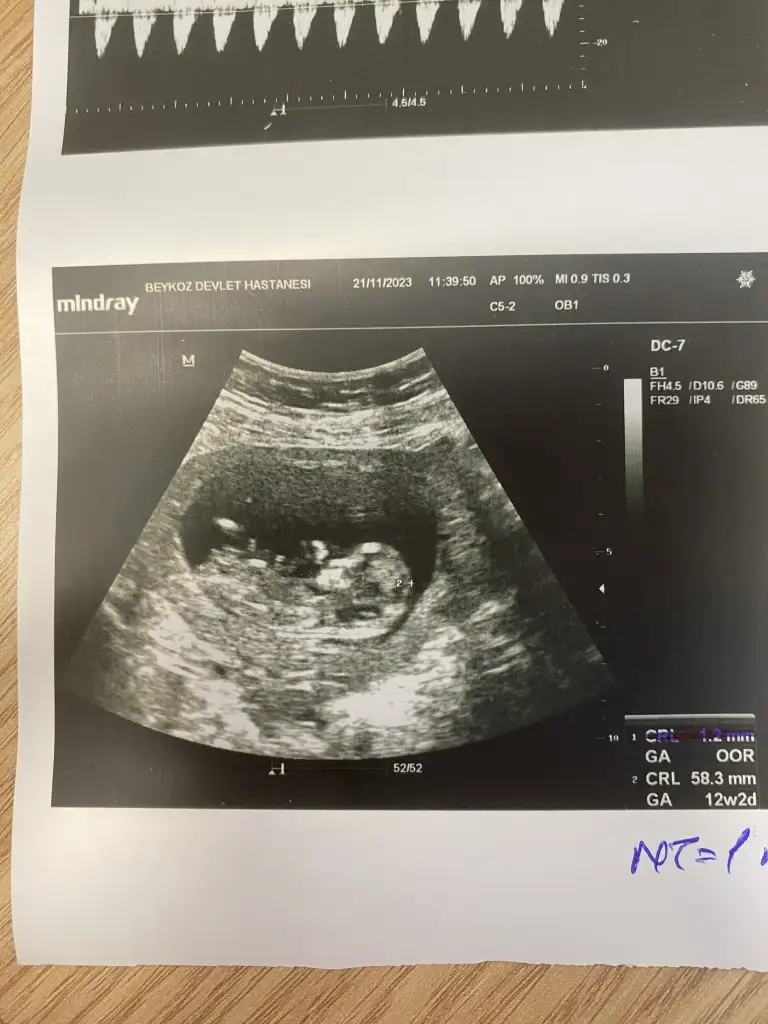

Benimkine de bakabilir misiniz doktorum 11+5te kız dedi 13+6da erkek dedi

İlk 3 fotoğraf 13+6

Son 2 fotoğraf 11+5